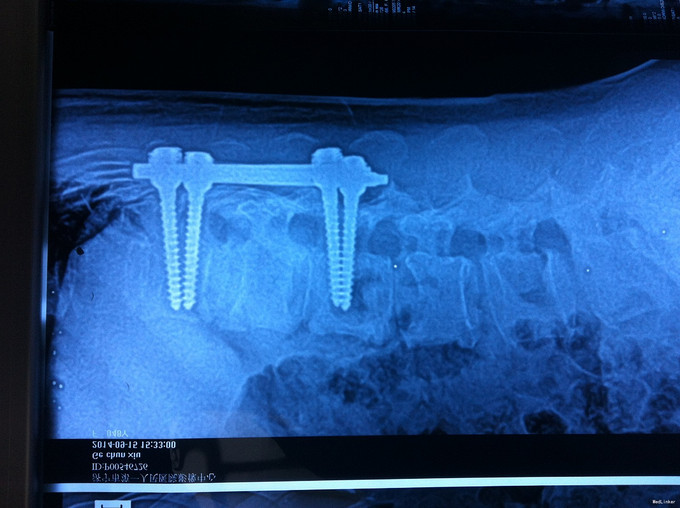

专科查体无下肢神经损伤表现:腰部叩痛,腰部活动受限,双下肢感觉无异常,双下肢肌力4-5级,双侧膝腱反射++,跟腱反射+,双侧巴氏征阴性, X-ray:腰1椎体骨折,累及前中柱,腰3椎体骨折。CT:腰1、3椎体骨折,累及中柱。MR:腰1、3骨折,新鲜骨折。影像学检查提示腰1椎体骨折较重。

诊断:腰椎骨折 腰1、3椎体 处理:1、完善相关辅助检查,明确诊断,有无手术指证; 2、完善手术评估,有无手术禁忌,手术风险及并发症; 3、在全麻下行腰1椎体后路撑开复位内固定术,腰3椎体压缩较轻,可卧床保守治疗。

随访:1、应常规术后1个月注意有无神经症状,及后凸畸形形成 2、卧床时间适度延长 讨论:多发腰椎骨折,是否选择同时撑开复位,较轻的还是结合保守治疗,如何选择